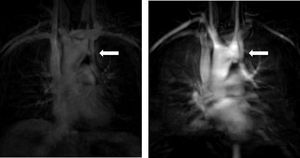

Aortic diameter, corrected for age and body size, is accurate for predicting aortic events, and is the principal risk marker for aortic dissection.1,5 An ascending to descending aortic diameter ratio above 1.5 signifies ascending aorta dilatation if descending aorta diameter is normal. There is another alternative to identifying aortic dilatation that correlates more closely with aortic diameter, because it adjusts aortic dimensions for body surface area (BSA); this is important due to the relatively short stature of patients with TS. This latter method involves estimating the aortic size index (ASI): aortic diameter (at the ascending aorta or at the site with the largest dimension)/BSA. It has been proposed that an ASI ≥2 cm/m2 identifies those who require close monitoring and an ASI ≥2.5 cm/m2 (as in Figure 4) requires aortic surgery to prevent aortic dissection.4,21,24,25

B.4. Aortic dissectionAlthough rare, aortic dissection is a major concern in TS. It has an estimated incidence of 40 cases per 10000 patients, but is often fatal. It occurs at a much earlier age; in the general population, the peak incidence of dissection occurs between ages 50 and 80 and in TS population median age is 35, with higher incidence rates at ages 20–29 and 30–39.2,26

Up to 90% of aortic dissections have predisposing CV risk factors (BAV, aortic dilatation and CoA) that can be identified with CMR imaging. HTN and pregnancy are associated with a higher risk of dissection, the former due to an association with increased aortic root diameter and the latter due to physiological adaptation, which imposes a higher cardiac workload.4,19